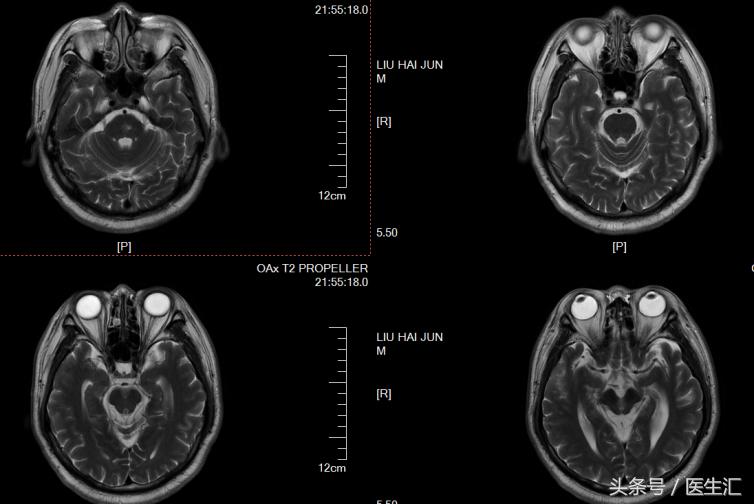

影像检查